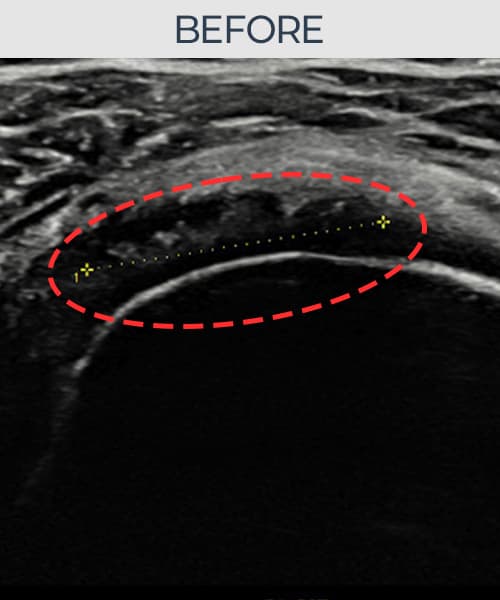

超音波検査にて腱板 部分断裂+靭帯損傷(11mm × 6mm (腱厚の約58%欠損))を確認。縫縮術施行後、腱の連続性が回復し、日常生活に復帰されました。

施術前

術前超音波にて腱板 部分断裂+靭帯損傷・肩棘上筋腱のエコー不連続と腱欠損(11mm × 6mm (腱厚の約58%欠損))を確認。術後超音波では断裂部位が再生組織で充填され、腱の連続性回復とエコーパターンの正常化が確認されました。

持続する肩痛で来院された患者様です。超音波検査にて腱板 部分断裂+靭帯損傷(欠損:11mm × 6mm (腱厚の約58%欠損))を確認し、超音波ガイド下で非手術的縫縮術を施行しました。術後は約4〜6週間のブレース装着の後、段階的なリハビリプログラムを実施。経過超音波で腱の連続性回復を確認し、患者様は無事に日常生活へ復帰されました。